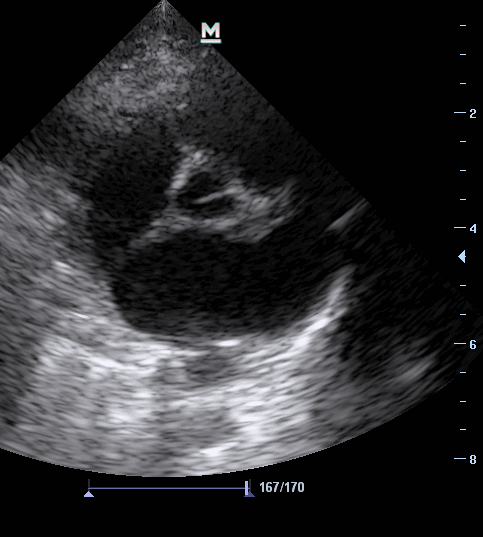

3. Трехмерная эхокардиография правого желудочка. В связи с неправильной формой правого желудочка, который, как раковина, прикрывает левый желудочек, результаты определения его объема и фракции выброса с помощью двумерной ЭхоКГ неточны. Точно определить эти параметры можно с помощью трехмерной ЭхоКГ. Этот метод более трудоемкий, но не зависит от конфигурации правого желудочка; валидность его доказана как в эксперименте на животных, так и в клинических исследованиях.

Больной с явно дилатированными правыми отделами сердца как проявление гемодинамически значимой нагрузки объемом. Диаметр отверстия трехстворчатого клапана, индексированный к площади поверхности тела, составил 28 мм/м 2 . Умеренная недостаточность трехстворчатого клапана, выявленная при цветовом допплеровском картировании из апикальной четырехкамерной позиции.

1. Двумерная эхокардиография. Морфологическая оценка трехстворчатого клапана, а также определение размера кольца трехстворчатого клапана при сканировании в плоскости четырех камер сердца позволяют установить, является ли трикуспидальная недостаточность органической или имеет функциональную природу. При наличии значимой вторичной недостаточности трех створчатого клапана, развившейся в результате легочной гипертензии, диаметр клапанного кольца, индексированный к площади поверхности тела, превышает 20 мм на 1 м 2 . Максимальный диаметр кольца трехстворчатого клапана при сканировании из апикальной четырехкамерной позиции измеряют сразу после зубца Р ЭКГ.